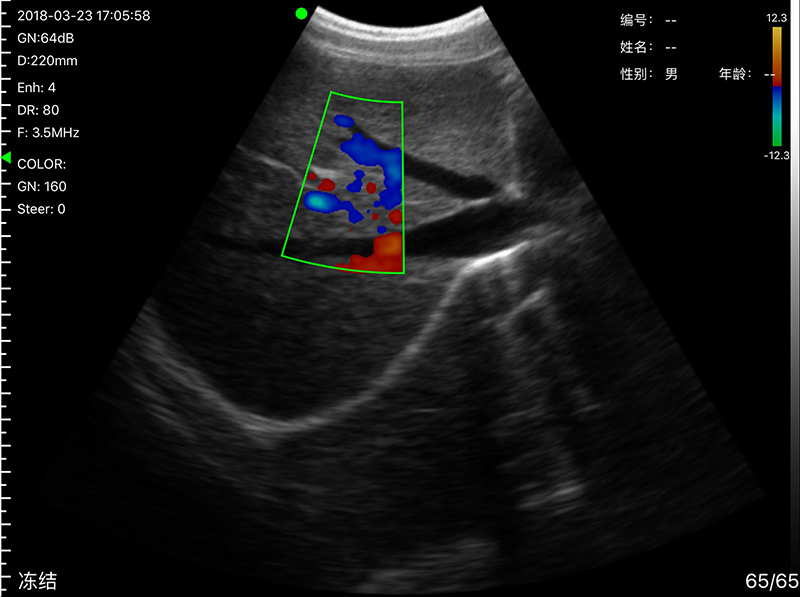

• Probe Head: R60 Convex+R13 Transvaginal

• Display mode: B, B/M, color doppler version with B+Color, B+PDI, B+PW

Convex head 3.2MHz/5MHz, 90/160/220/305mm, R60

• Image Adjust: BGain, TGC, DYN, Focus, Depth, Harmonic, Denoise, Color Gain, Steer, PRF